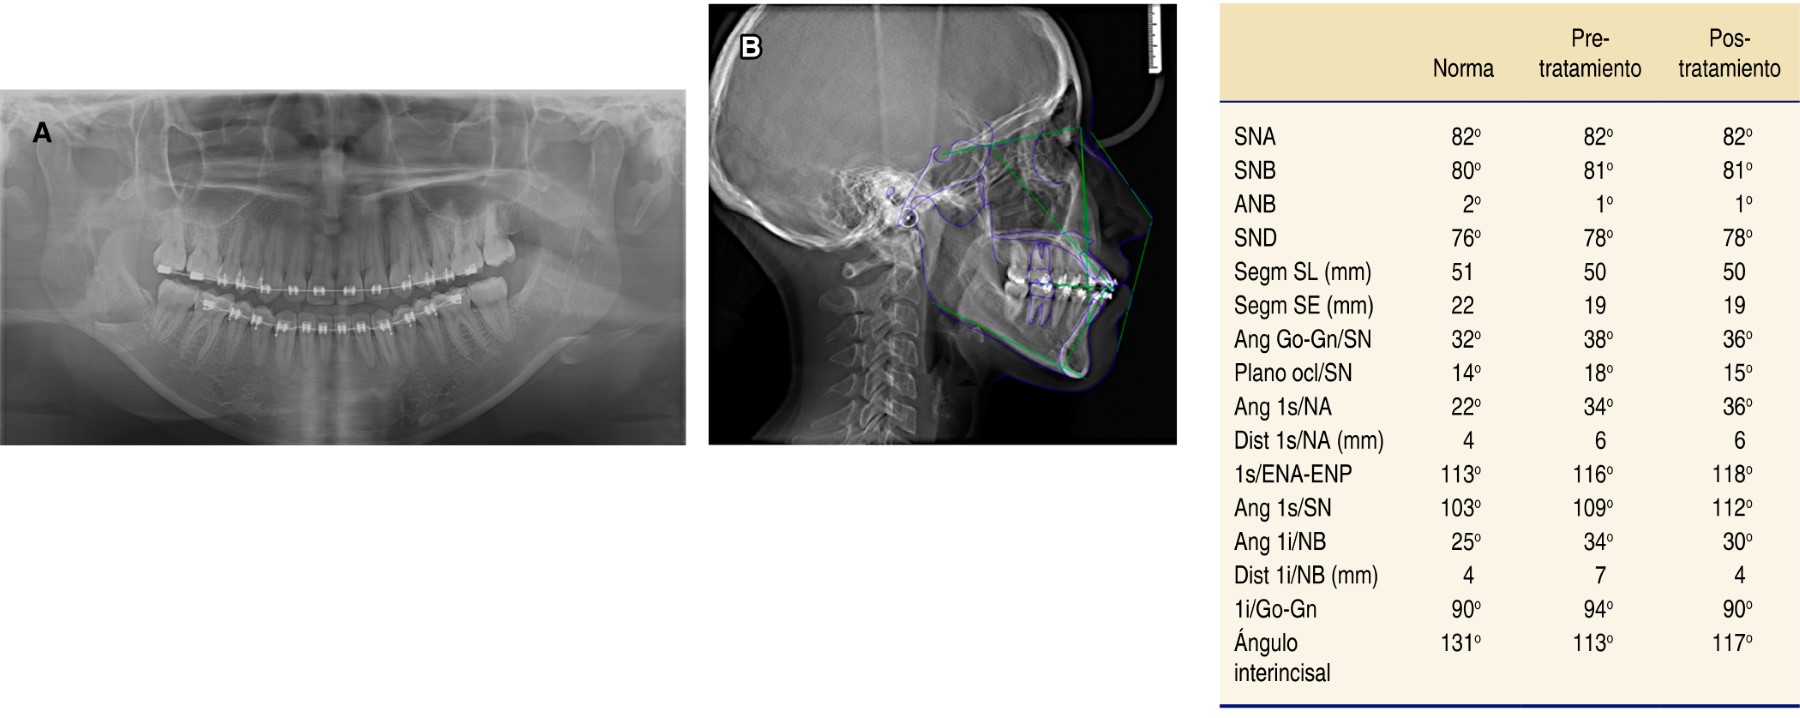

En la radiografía panorámica se observaron 28 dientes permanentes erupcionados y terceros molares en proceso de erupción; la longitud radicular es de 3:1; los senos, cóndilos y ramas mandibulares aparentemente simétricas, sin presentar alguna alteración (Figura 3A).

En la radiografía lateral de cráneo –de acuerdo con el trazado cefalométrico de Steiner– la paciente mostró un patrón esquelético clase I. El plano mandibular aumentado indica un patrón de crecimiento vertical, proinclinación de incisivos superiores (1s/SN 109o) y proinclinación de incisivos inferiores (IMPA 94o) (Figura 3B).

Figura 3